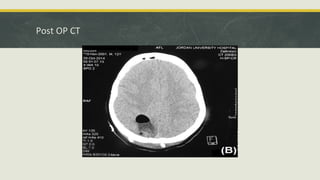

Post OP CT

• #39 This image shows a craniotomy defect in the right side with adjacent postoperative changes including; subgaleal changes. some pneumocephaly. a resection cavity within the right parietal lobe; it does haves some air-fluid level, and some hyper-density which suggest a bit of a hemorrhage. the size of the resection cavity is much smaller than the original size of the lesion.